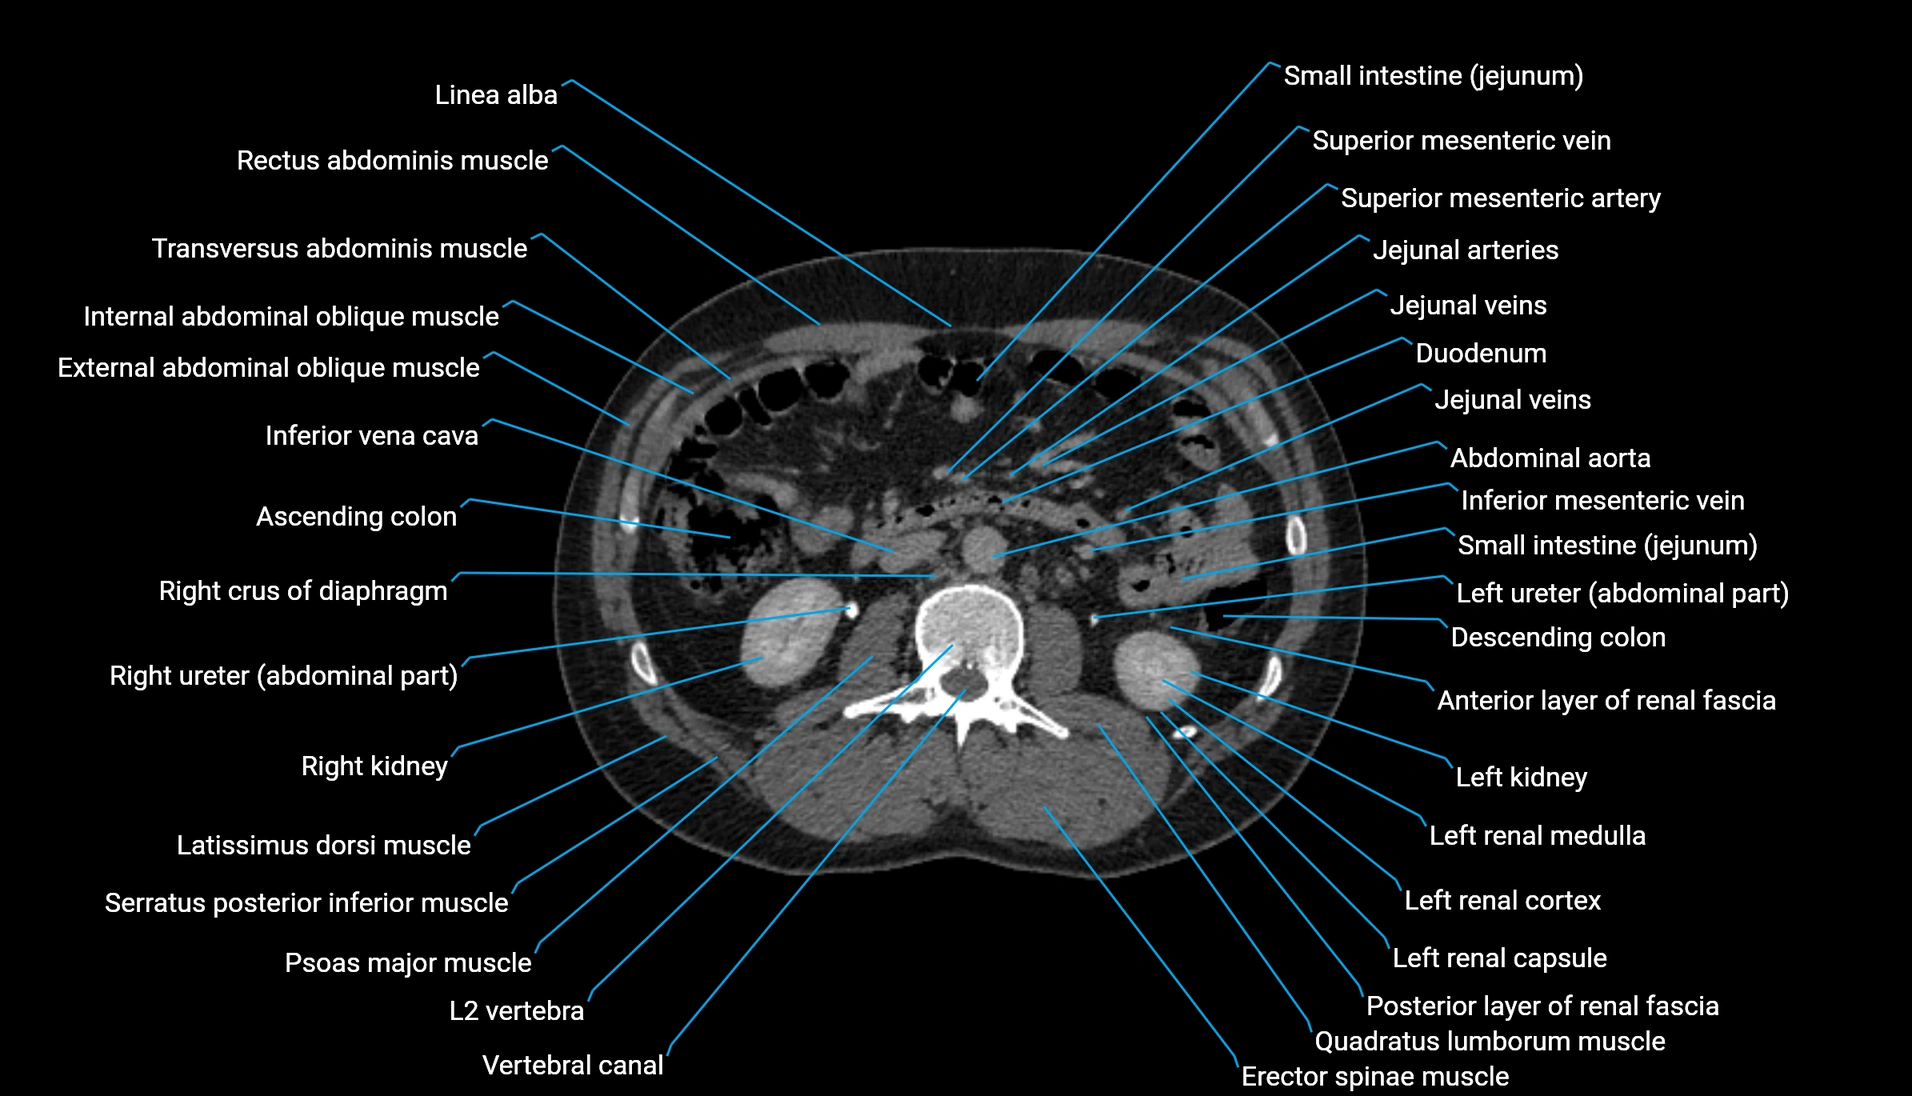

CT Appearance

Non-contrast CT:

-

Demonstrates cortical bone of acetabular rim in excellent detail

Detects fractures, dysplasia, retroversion, or bony overcoverage (pincer impingement)

3D reconstructions used in preoperative hip surgery planning

CT image